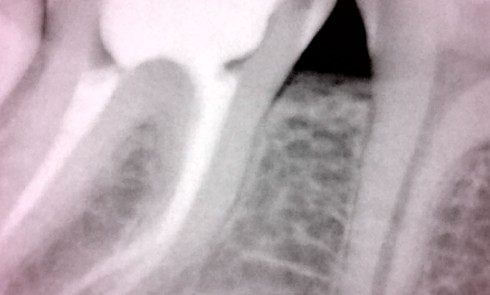

Article réservé à nos abonnés L’endocouronne : état des données actuelles

La restauration des dents traitées endodontiquement et ayant subi une perte de substance importante demeure un défi à relever. Ce...

Article réservé à nos abonnés L’obturation canalaire avec une nouvelle famille de biomatériaux… en toute simplicité (partie 2)

STÉPHANE SIMON Professeur des Universités (Paris Santé), exercice libéral limité à l’endodontie. Grand leader d’opinion et d’enseignement en endondontie, Stéphane...